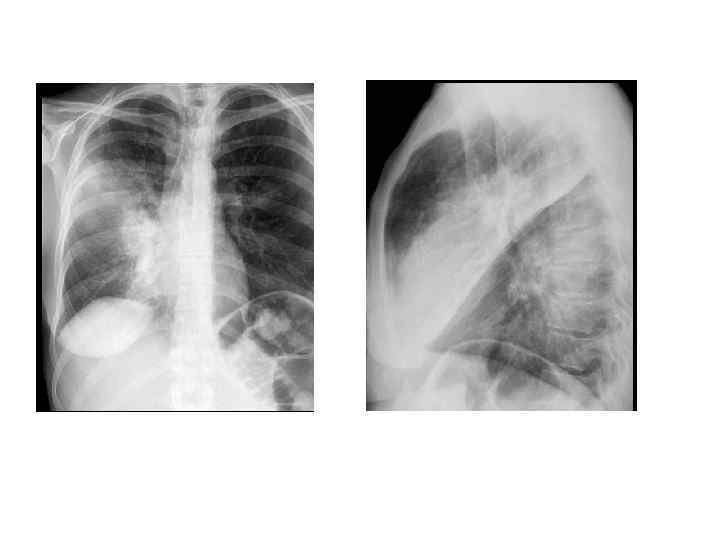

Критерии тяжелого течения ВП • • • Двух- и многодолевое поражение ОДН (Ра. О 2 < 60 мм рт. ст. или Sat 02 < 90%) Шок (снижение АД <90/60) ОПН Нарушение сознания

Тяжелая ВП Летальность при тяжелой внебольничной пневмонии 20 -60% Основные причины смерти: -Рефрактерная гипоксемия -Септический шок -СПОН

Причины перевода пациентов в тяжелой пневмококковой пневмонией в ОРИТ 222 пациента Многодолевая пневмония – у 30% Причины перевода в ОРИТ: • ОДН - 154 пациента • Септический шок – 54 При дальнейшем ведении: • Необходимость в ИВЛ – 186 (84%) • Септический шок - 170 (77%) • Адекватная АБТ – 92, 3% • Летальность – 29% Mongardon et al. Critical Care 2012, 16: R 155 http: //ccforum. com/content/16/4/R 155